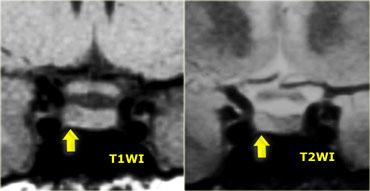

Các hình ảnh này minh họa một trường hợp điển hình: trên chuỗi xung T1W, tổn thương có đường kính khoảng 3-4 mm, giảm tín hiệu nhẹ so với mô tuyến yên bình thường, nằm trong tuyến yên.

Trên chuỗi xung T2W, tổn thương tăng tín hiệu nhẹ.

Chẩn đoán phân biệt: u tuyến yên vi thể hoặc nang khe Rathke (hai thực thể này có thể không phân biệt được với nhau).

Độ nhạy của MRI không tiêm thuốc tương phản từ trong phát hiện u tuyến yên vi thể vào khoảng 70%.